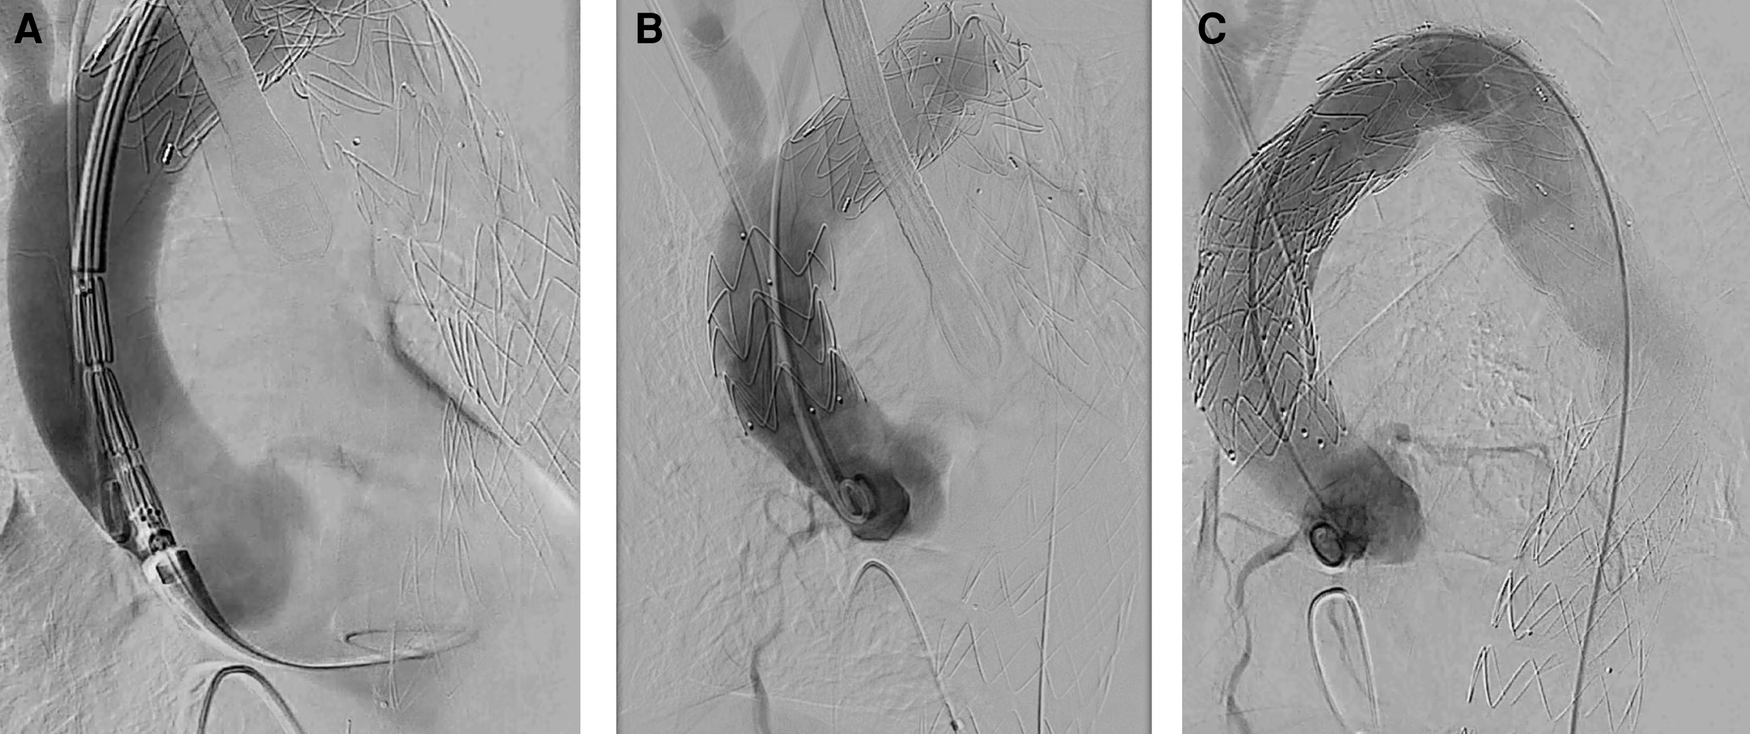

Figure 2

CTA after TEVAR and consecutive retrograde ATAAD. (A) Entry proximal of TEVAR stent graft. (B) Dissection involving the ascending aorta and the aortic arch. (C) 3D reconstruction.

After analyzing the CTA, iatrogenic ATAAD with entry location at the proximal edge of the TEVAR prosthesis in the descending aorta was confirmed, most likely caused by the tip of the stent. Entries in the aortic arch or the ascending aorta could not be identified. According to the new TEM classification by Sievers et al., this resulted in “A, E3, M3+” (A = type A dissection according to Stanford, E3 = entry in the descending aorta, M3+ = peripheral malperfusion with clinically relevant malperfusion) (10). Landing zone length of the ascending aorta was 72 mm, proximal landing zone diameter was 33 mm, and distal landing zone diameter was 28 mm. Preoperative CTA (SOMATOM Definition Flash, Siemens®, Erlangen, Germany) is shown in Figure 2. Imaging of the intracranial vessels was not available.